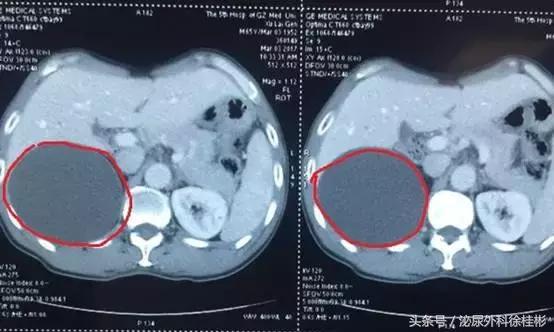

红色圈圈所指就是囊肿的位置

一听到“肿”字徐大叔心里就慌了,囊肿囊肿,会不会跟肿瘤有关系啊。于是一刻也没耽搁,赶紧到肾内科咨询。医生看了片子之后告诉徐大叔,囊肿和癌不一样,但目前囊肿比较大,直径有5-6cm,需要尽快治疗。